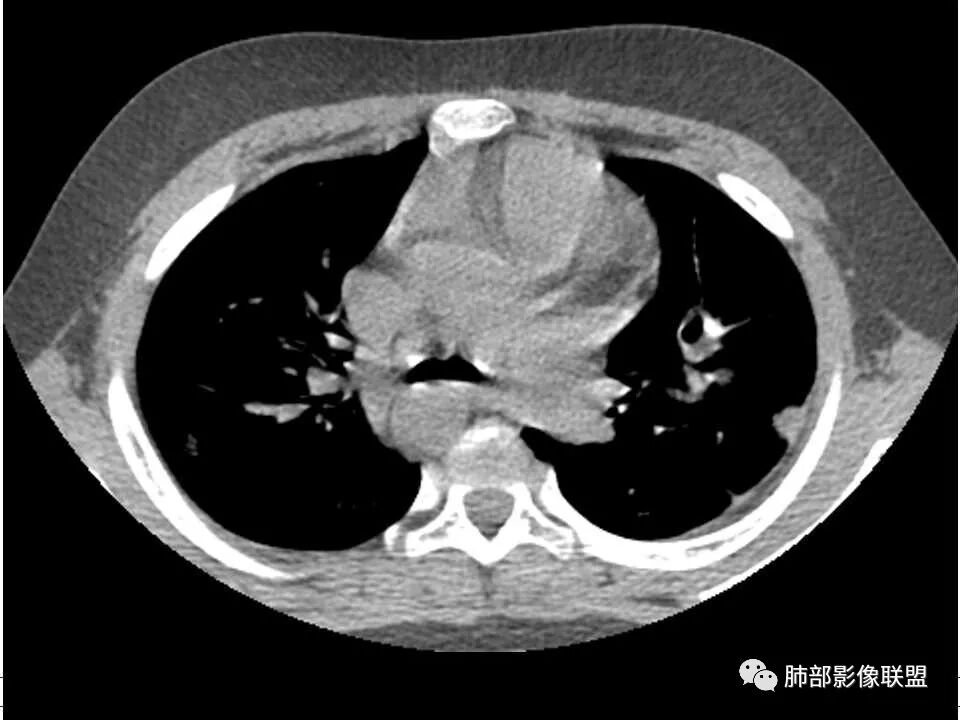

患者儿童,因右下肢疼痛伴肿胀14天就诊。病程中有发热及伴随症状。膝关节MRI提示右侧膝关节及右髌骨髁异常信号影,右膝髌上囊及关节腔内少量积液。胸部CT:双肺胸膜下多发结节影,部分结节空洞形成,且结节周围可见血管集束征。综合考虑血源性脓毒性肺栓塞、坏死性肺炎。右侧骨髓炎、血播性金葡菌肺炎,鉴别其他特殊感染及血管炎。

胸部ct:双肺多发空洞,结节,外带下叶为主,空洞内外光滑,有血管滋养征,综合病史及影像考虑脓毒性肺栓塞,结合病史,金葡可能性大。

2.双肺多发片影,随机分布,多空洞或囊腔,胸膜下多楔形影,气道未见受累等等符合脓毒血症影像学表现,尤其是金葡。

1. 多发胸膜下外周结节、< 3 cm 的楔形影和滋养血管征 CT 表现;

4.经恰当的抗生素治疗,肺部浸润影吸收。滋养血管征为一支血管影连接肺部周边病灶,在 2/3 以上患者出现,可作为高度提示 SPE 的征象。